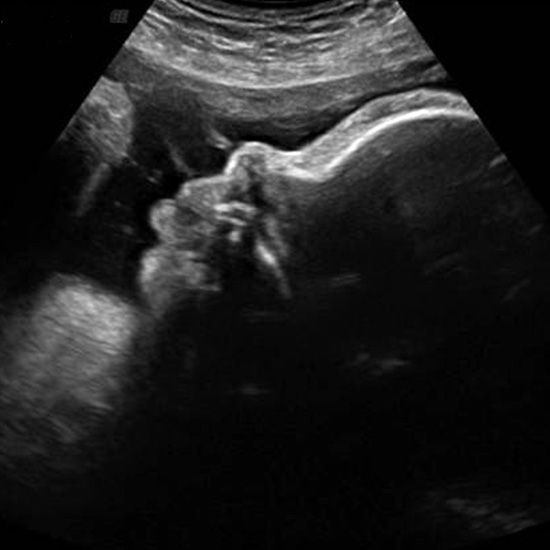

When Does Baby's Head Go Down. Your baby will turn his head a bit when he reaches the bottom of your pelvis. Find your baby’s head by feeling for a small bowling ball.

Your baby will turn his head a bit when he reaches the bottom of your pelvis. Feel their bottom or legs above your belly button. Dee89loves due june 26 (girl);

Based on the percentages above, figure out how likely it is that baby is head down and begin feeling gently for their head above your pelvis. Continue with the pelvic stabilizing exercises and psoas release, and any myofascial releases ( standing or. Your baby may be head down if you can:

During pregnancy at 30 weeks, baby’s position is most likely head down. Back sleep is still the safest way for your baby to sleep. A baby starts moving around from the 14 th week of pregnancy and these initial movements are called ‘fluttering’ or ‘quickening.’.